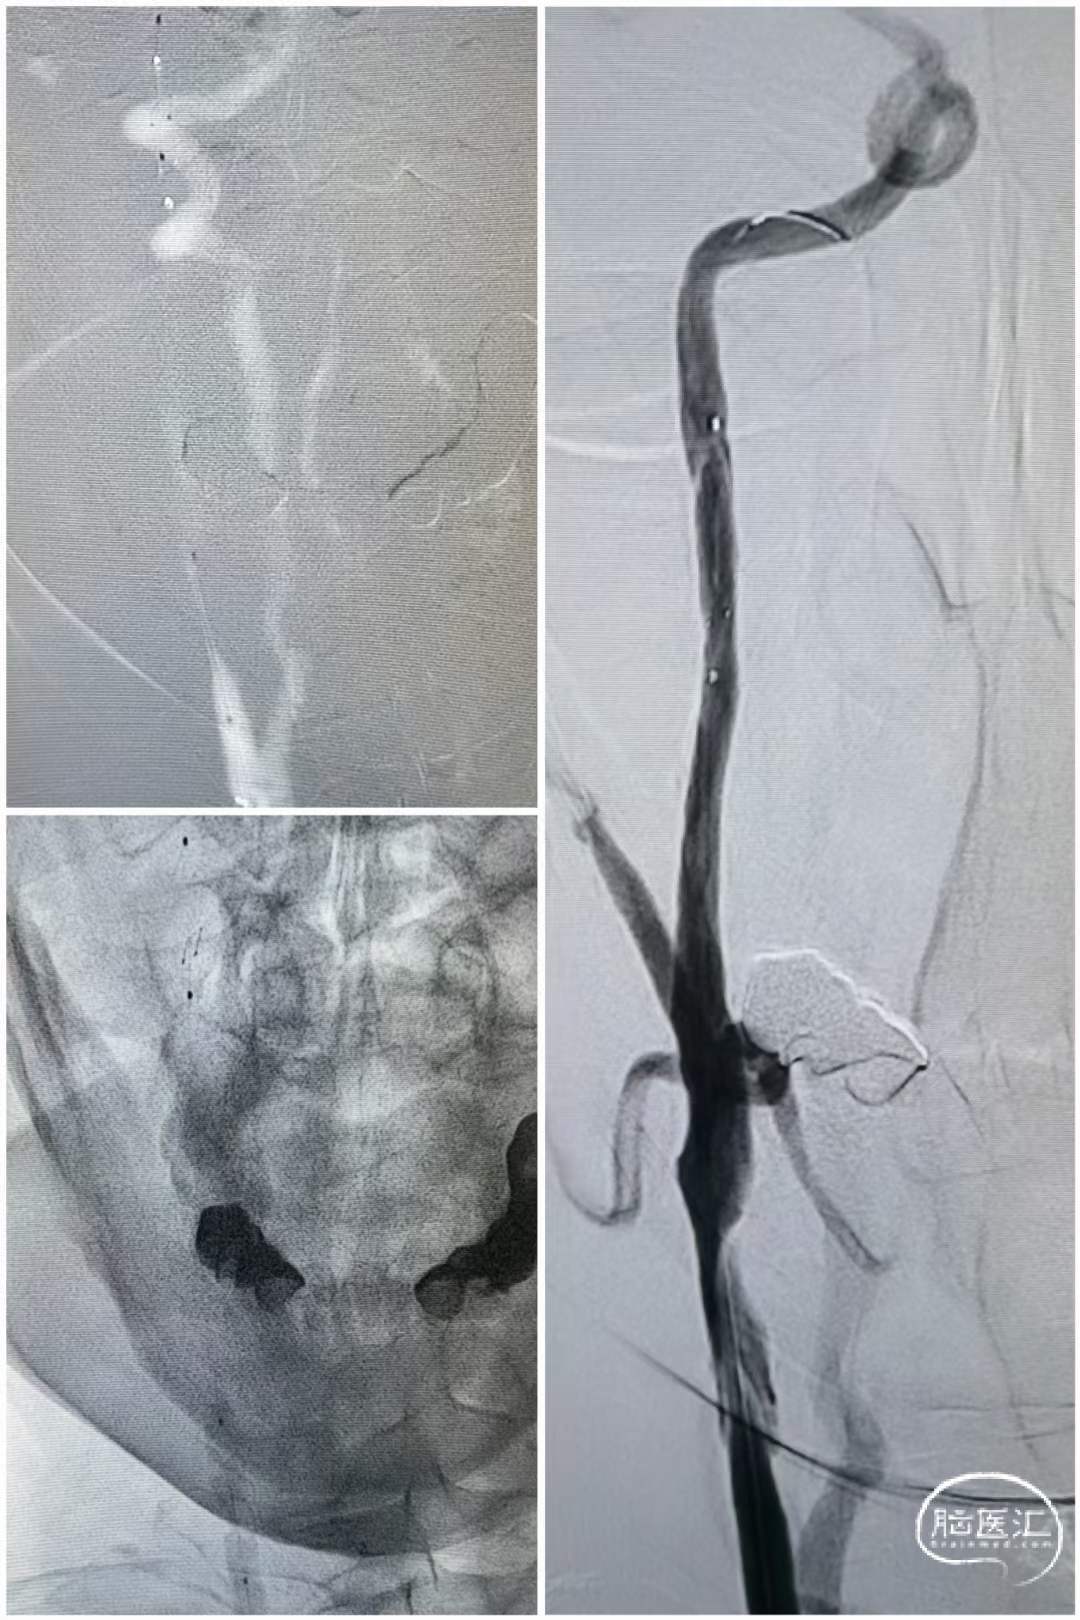

术前造影

造影可见:右侧颈总动脉慢性闭塞,左侧颈内动脉、颈总动脉串联狭窄。